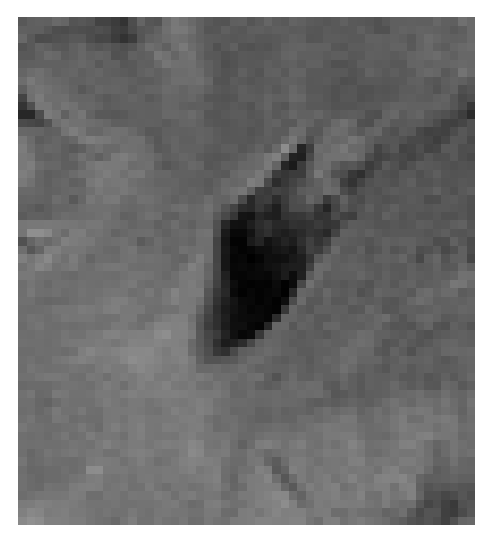

Figure 3: Examples of Reconstruction Results. Rows 1 and 3: The Ground truth (GT) fully sampled image, the reconstructed images obtained by the three models (1-3), NPB-REC, baseline, E2E-VarNet trained with Dropout, and the Std. map derived from our method for acceleration rates R=4𝑅4R=4, R=8𝑅8R=8, respectively. Rows 2 and 4: The corresponding annotated ROIS of the edema and resection cavity.

Fig. 3 presents examples of reconstruction results obtained by (1) our NPB-REC approach, (2) the baseline, and (3) Monte Carlo Dropout, for equispaced masks with two different acceleration rates R=4𝑅4R=4 and R=8𝑅8R=8. Table 1 presents the mean PSNR and SSIM metrics, calculated over the whole inference set, for the three models. our NPB-REC approach achieved significant improvements over the other methods in terms of PSNR and SSIM (Wilcoxon signed-rank test, pmuch-less-than\ll1e-4). The improvement in the reconstruction performance can be noted both quantitatively from the metrics especially for masks with acceleration rate R=8𝑅8R=8 and qualitatively via the images of annotations, where our results shows less smoothness than that obtained by Dropout.